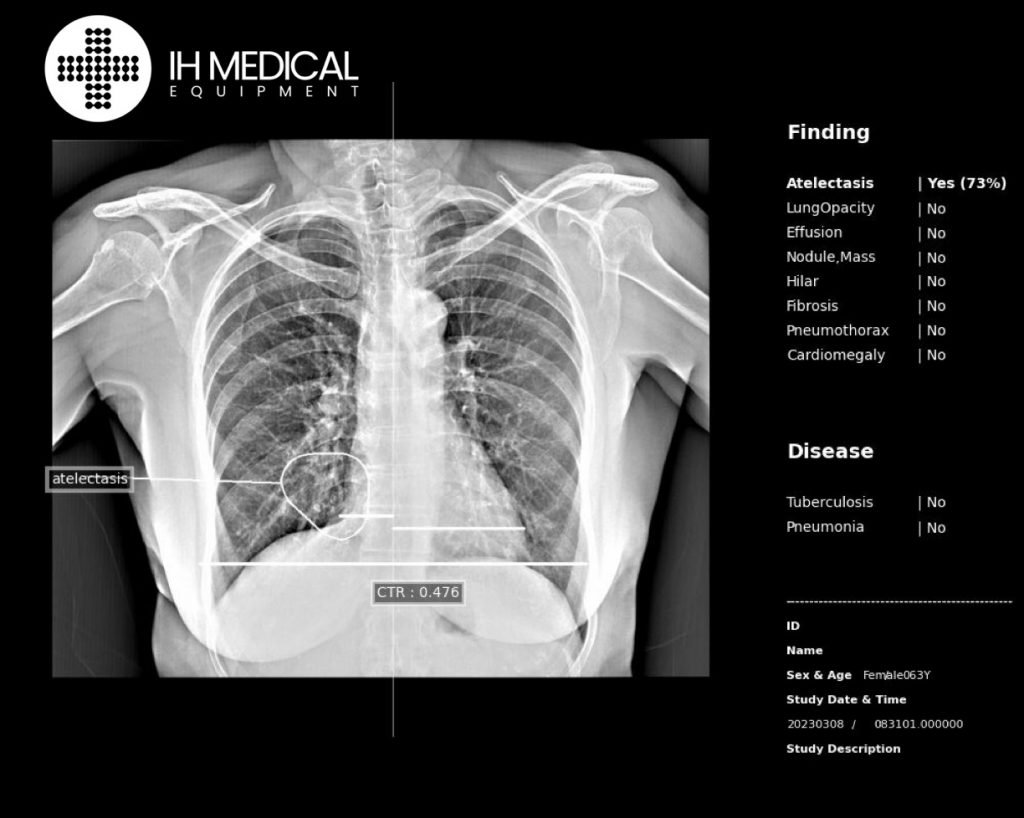

Ai Radiologist Assistant Detection

- Chest Abnormalities: Atelectasis, Lung Opacity, Effusion, Mass, Pneumothorax, Cardiomegaly, Tuberculosis, Nodule

- Diseases: Tuberculosis, Pneumonia

- Lesions: Contour Plot, Heat map, Bounding Box

- Others: Cardiothoraxic Ratio